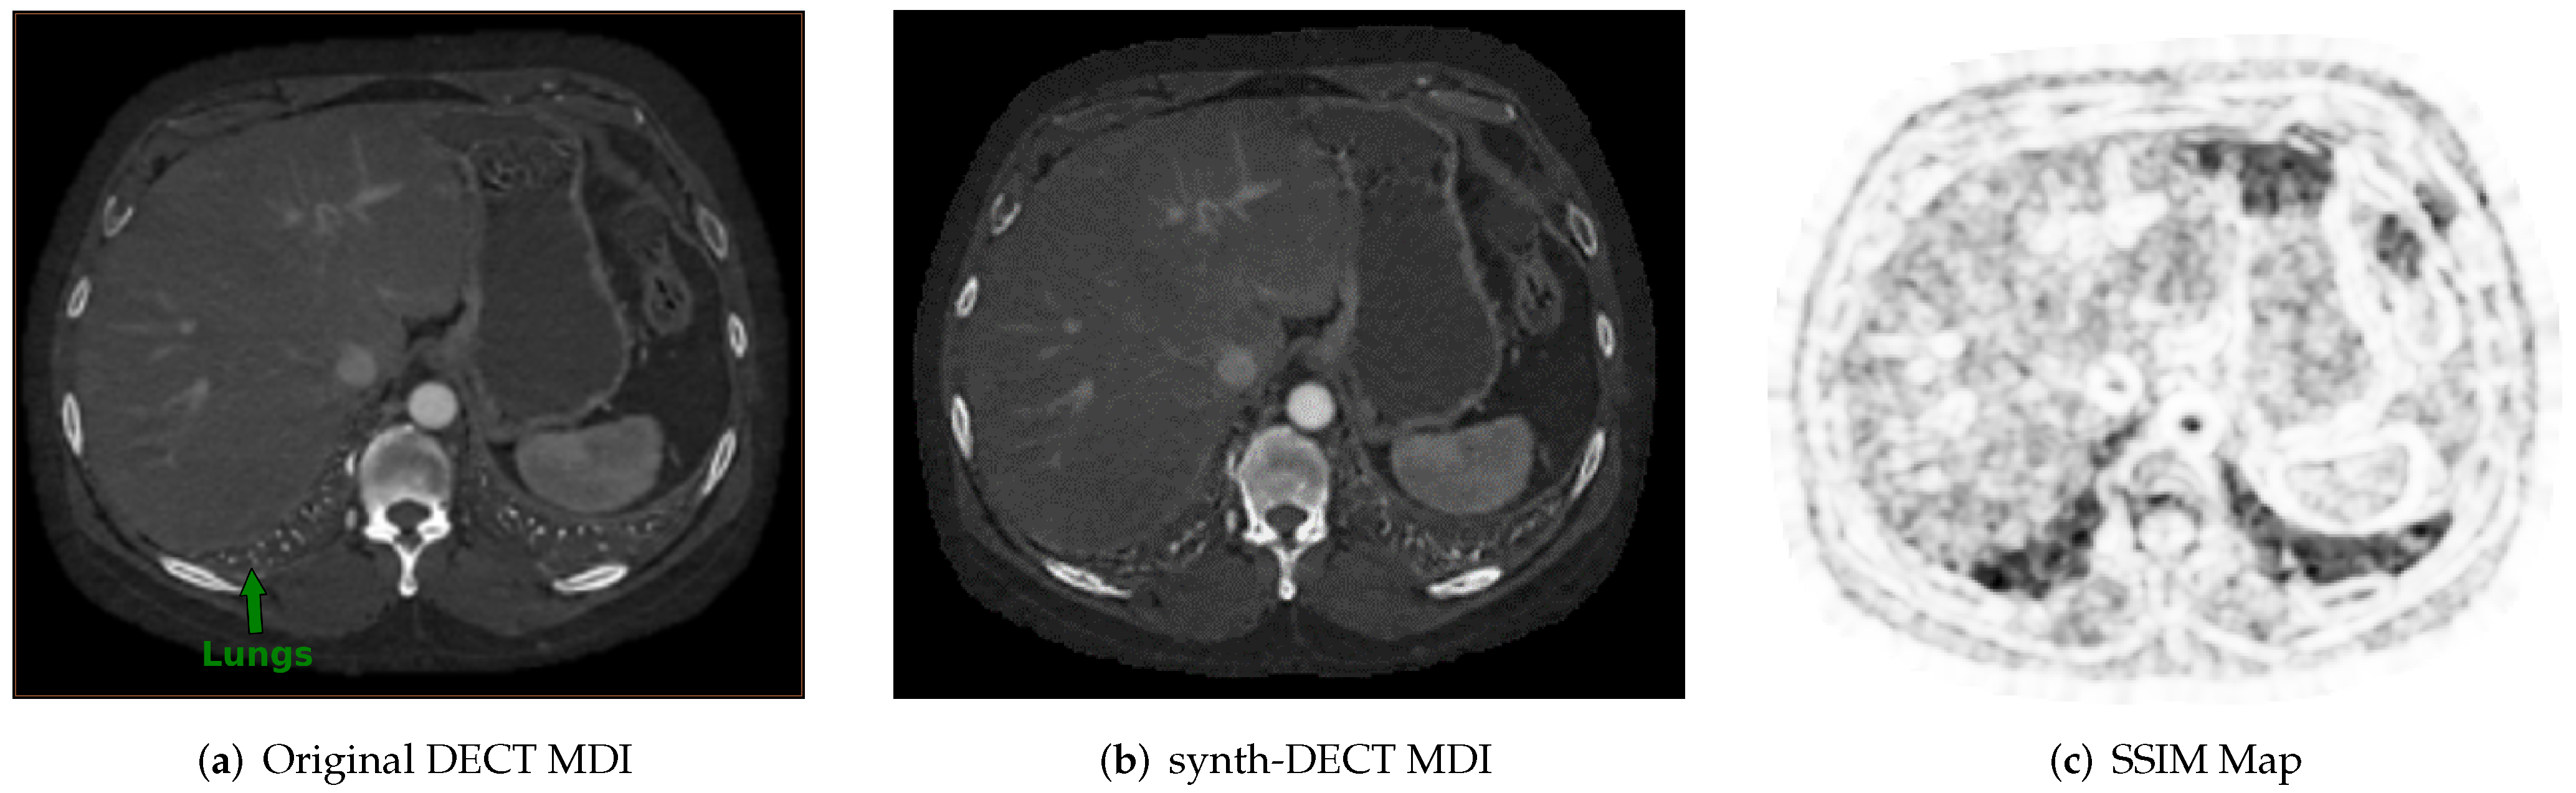

Figure 3. Example cross sectional axial slices from the test dataset used for Pix2Pix. (a) The original dual energy CT material density iodine (DECT MDI). (b) The synth-DECT MDI for the slice shown in (a). The global structural similarity index (SSIM) for the scan from which the slices were taken was computed to be 0.92. (c) This figure displays the local SSIM scores for each pixel of the slices in (a,b) as an image: The dark areas depict small values of the SSIM, which indicates a large difference between the original and synthetic image. The bright regions show large values of the SSIM or areas that were the most similar between the original and synthetic.

Across the nine test set scans, the average SSIM was computed as 0.94 ± 0.014 . Figure 3a,b shows an example cross-sectional axial slice from a single patient CT scan in the Pix2Pix test set. Subjectively, the original and synthetic slices in Figure 3a,b appear similar, but upon closer inspection, the base of the lung field pointed at in Figure 3a was blurred in the synthetic slice. Similar blurring in the lung field was observed across all test set scans. Figure 3c displays the local pixel level SSIM values computed between the slices shown in Figure 3a,b. The darker portions in Figure 3c point to air-filled cavities where the computed SSIM decreased. One reason for the low local SSIM within the air-filled cavities is that the effective attenuation of air within the lungs is neither similar to the two basis pairs, water or iodine, which were used to reconstruct the DECT image types. When the effective attenuation is unlike the two basis materials, a negative pixel value is assigned in the original DECT MDI scan.